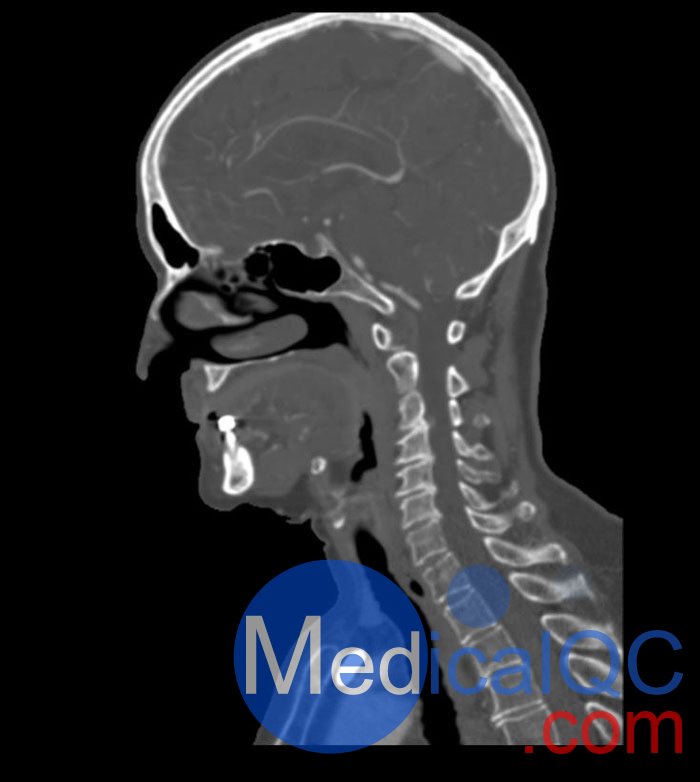

WEK51-02 CT血管造影頭模,WEK51-02 CTA頭部模型模擬動(dòng)脈期造影劑增強(qiáng)頭部(CT 血管造影)。頸部和上胸包括主動(dòng)脈弓和第五胸椎。頂點(diǎn)被包括在內(nèi),直到皮膚水平以下約 0.5 厘米。胸廓模體部分不包括通常不屬于 CTA 檢查的肩部和背部部位。

頸動(dòng)脈內(nèi)動(dòng)脈兩側(cè)鈣化,右側(cè)中度狹窄。否則,模體沒有明顯的血管病變。

該模型可用于 CT(包括 CBCT)以評(píng)估和優(yōu)化 CTA 成像性能和后處理應(yīng)用,例如血管分割,包括支持 AI 的應(yīng)用。它也非常適合培訓(xùn)目的。

該模型提供了對(duì)血管結(jié)構(gòu)、軟組織和骨組織的詳細(xì)和逼真的模擬,包括淋巴結(jié)等小細(xì)節(jié)??障吨刑畛渲s-160的纖維素-聚合物復(fù)合材料。

對(duì)頭頸部血管進(jìn)行逼真的模擬,直至主動(dòng)脈弓、骨骼和軟組織。兩側(cè)頸動(dòng)脈分叉處頸內(nèi)動(dòng)脈鈣化,右側(cè)輕度狹窄。

WEK51-02 CT血管造影頭模,WEK51-02 CTA頭部模型成像效果圖: